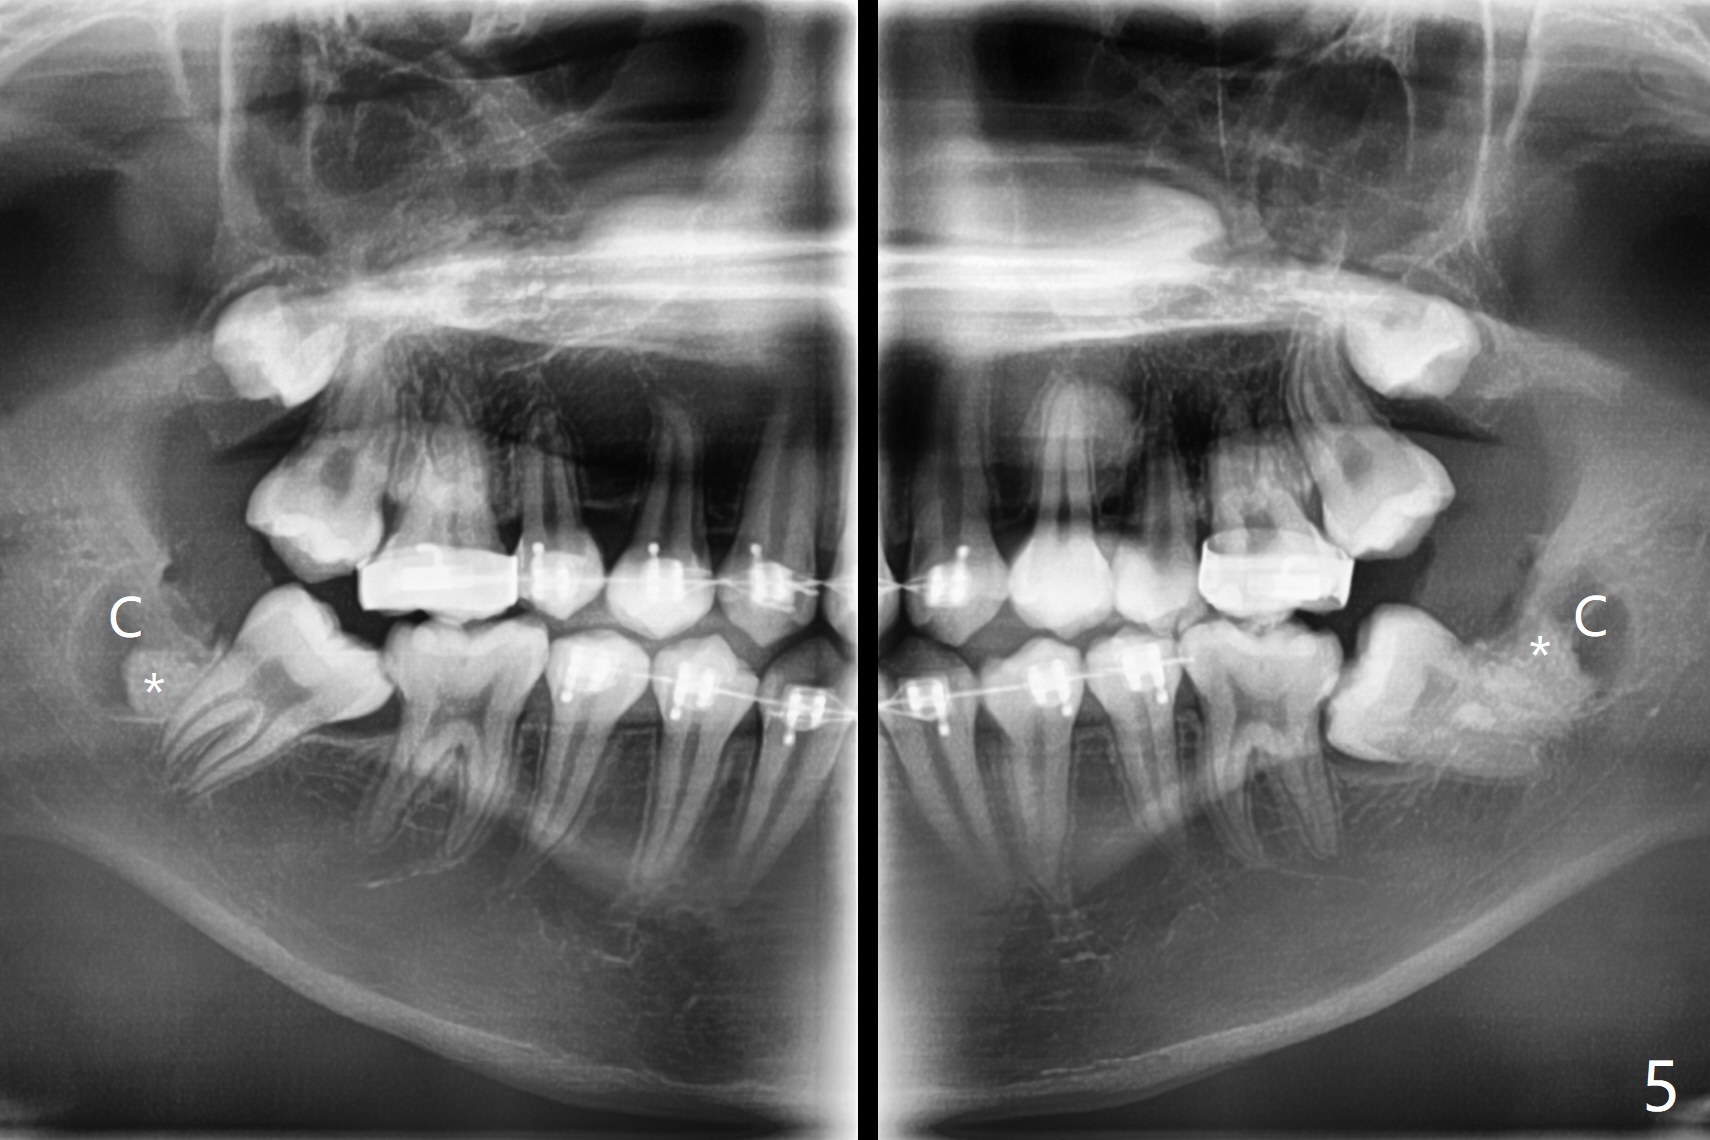

13岁男在矫正医生诊所矫正三年(上中切牙牙根短,图一),转来拔除下颌智齿以助于第二磨牙upright。左侧先拔除,切除三个小块颊侧骨板,保留其中一个与异体骨一起植入牙槽窝近中部分。右侧拔除时,索性切除一个大块颊侧骨板(图二),智齿拔除后,近中牙槽窝放置异体骨(皮质,图三,五:*),远中胶原塞(C),放回颊侧骨板(图四)。Return to Plug Xin Wei, DDS, PhD, MS 1st edition 11/03/2020, last revision 11/03/2020